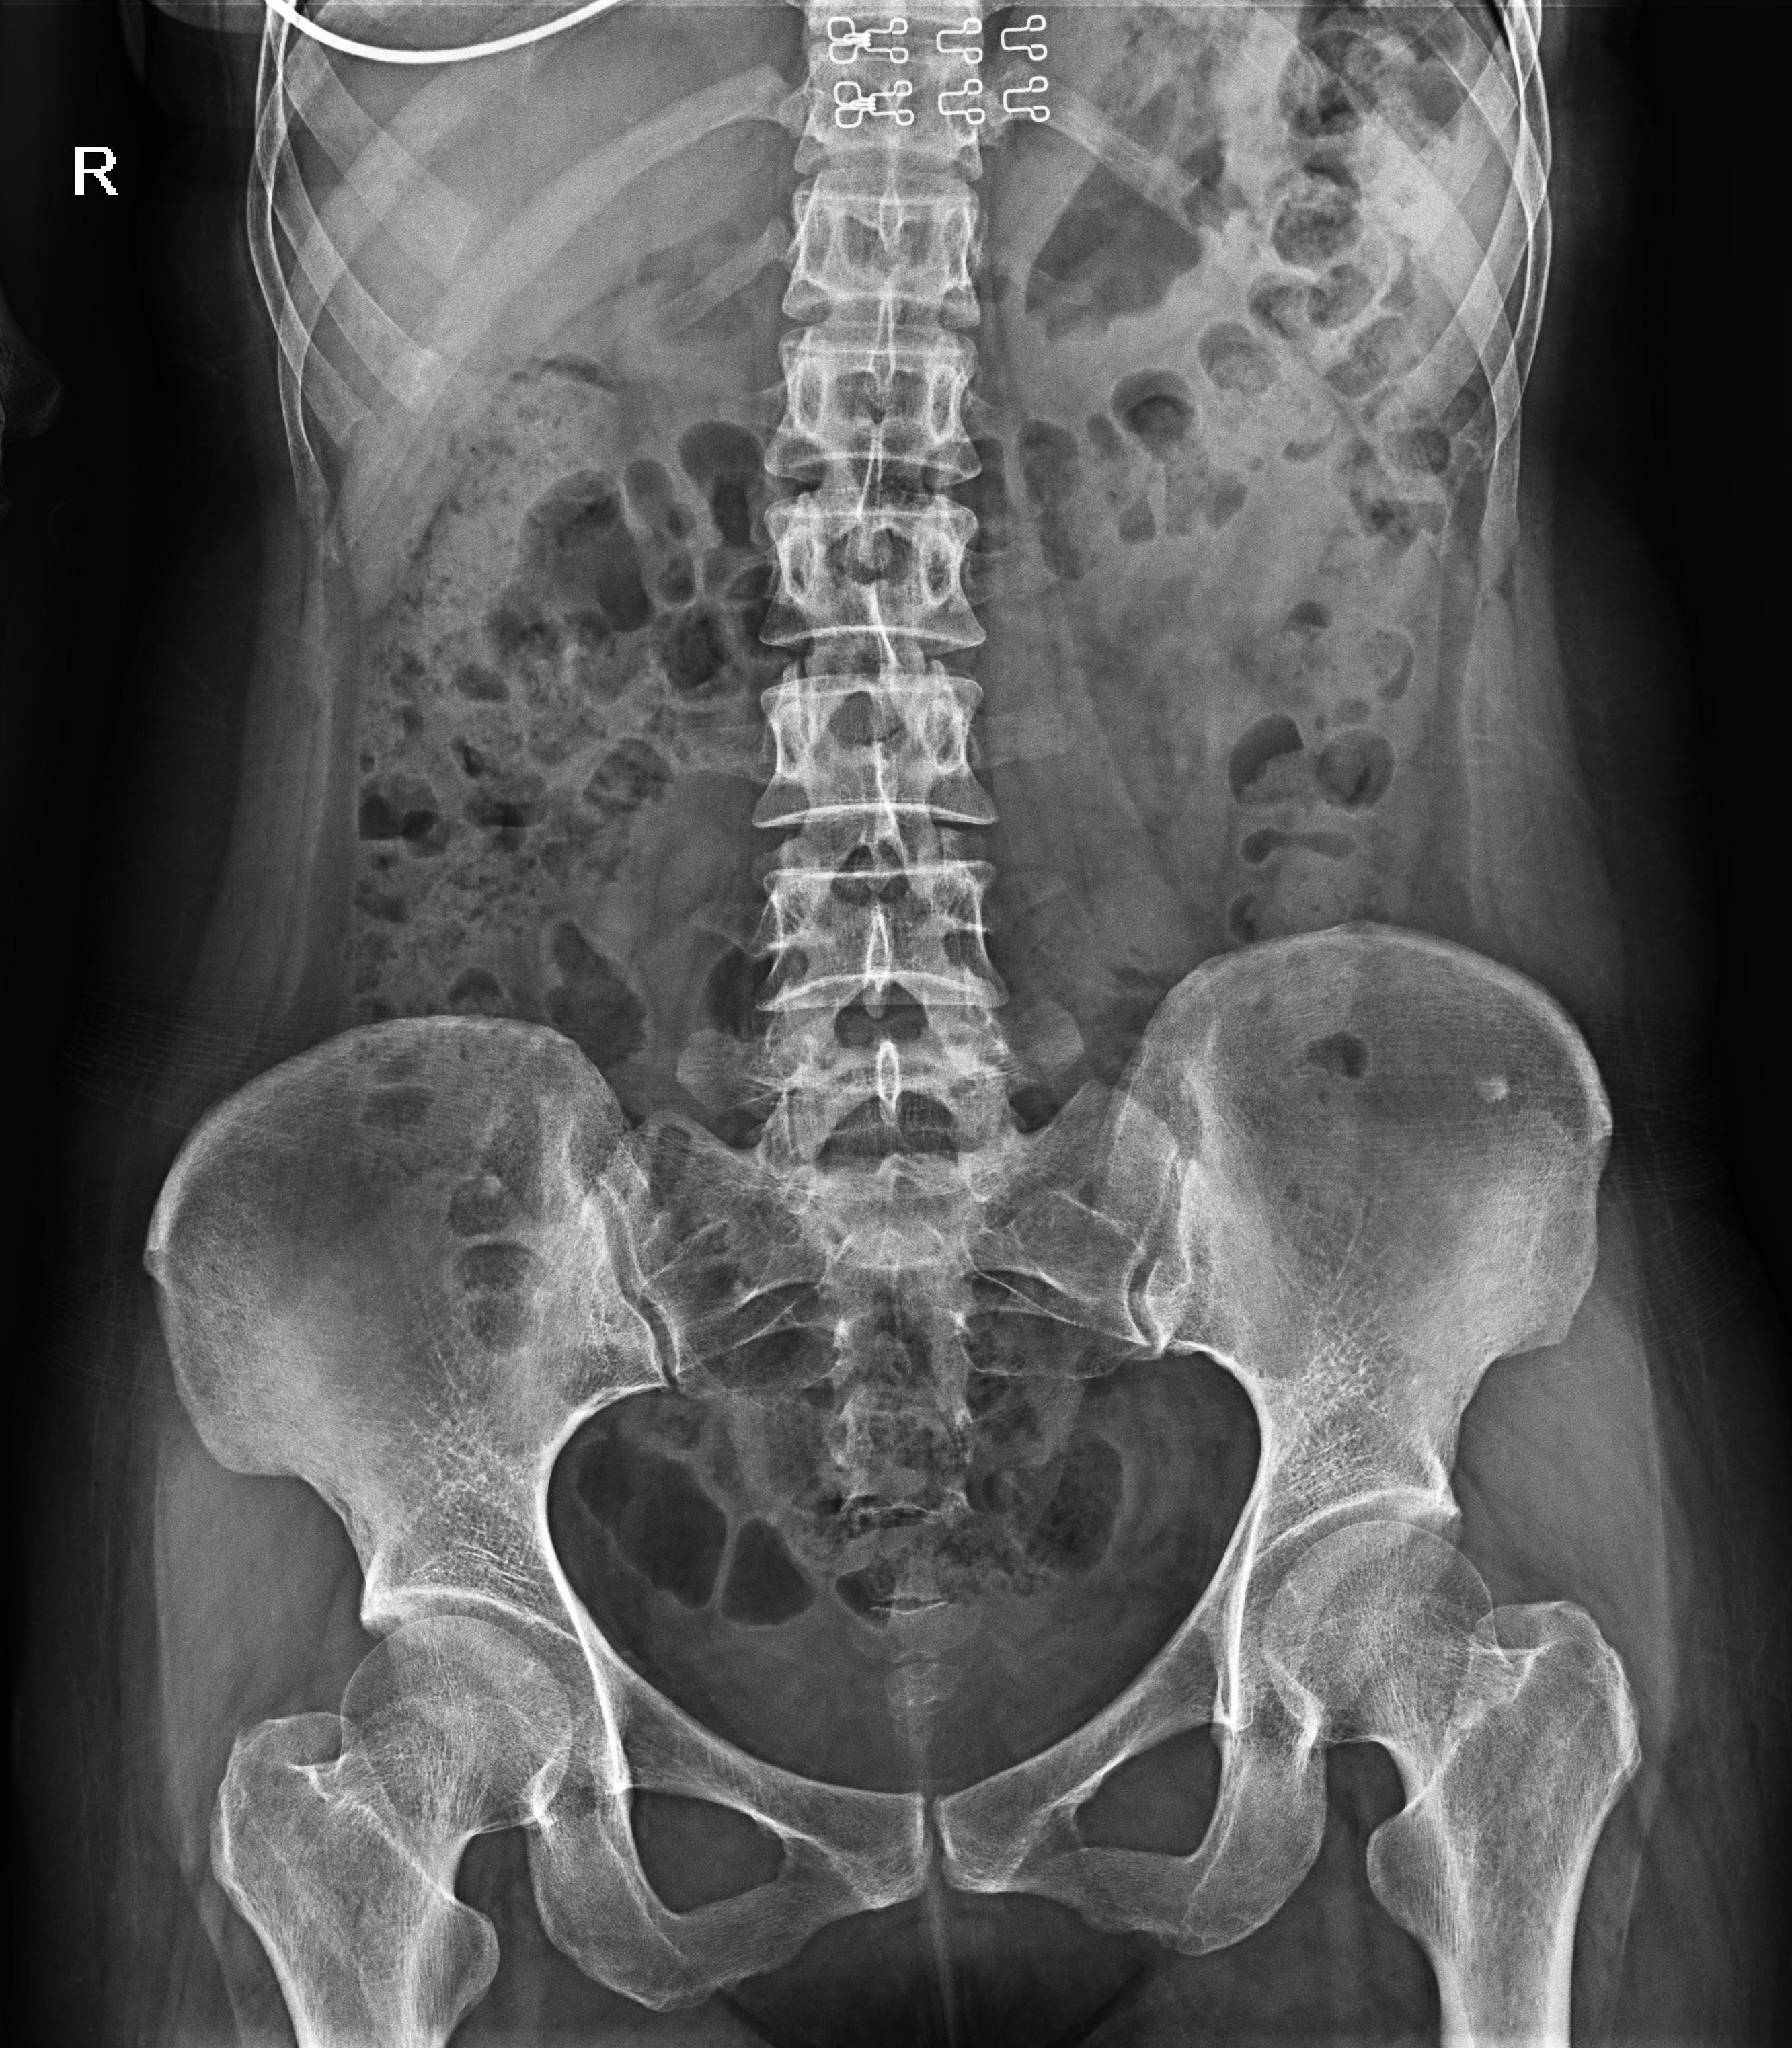

普利德醫(yī)療自主研發(fā)的新一代數(shù)字化X線透視攝影系統(tǒng),可應(yīng)用于DR攝影、數(shù)字透視、數(shù)字造影以及可視化精準(zhǔn)DR拍片等多種臨床X線檢查領(lǐng)域。

● 17*17英寸的超高清像素動態(tài)平板探測器,更大的視野范圍,無需移動即可觀察整個動態(tài)過程,避免拖尾、噪聲對圖像的影響;

● 高效動態(tài)平板技術(shù),圖像不會有幾何畸變,提供高分辨率和精確的圖像,為醫(yī)生臨床診斷提供精準(zhǔn)依據(jù);

● 最高幀速可達30幀/秒,動態(tài)采集清晰流暢,避免漏診、誤診情況的發(fā)生;

● 在可視過程或回放過程中,如發(fā)現(xiàn)疑似病灶,可進行毫秒級高清點片,隨時抓取單幀圖像,精準(zhǔn)捕抓病灶。